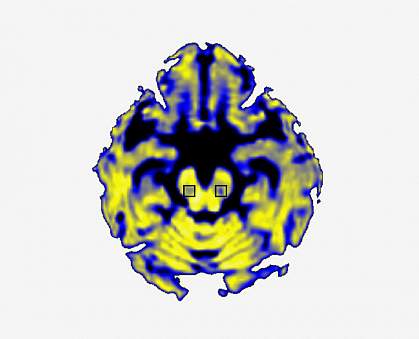

One possible biomarker is the amount of “free” water outside of cells in the brain. A technique called diffusion MRI can distinguish between water contained in brain cells and free water in a region. Previous studies have shown that there’s more free water in the substantia nigra of people with Parkinson’s than those of healthy people.

Using diffusion MRI, a research team led by Dr. David Vaillancourt at the University of Florida in Gainesville recently showed that free water in the substantia nigra increased over the course of one year in people with Parkinson’s disease but not in controls. In their latest work, the group tracked free water in the substantia nigra over a four-year period. The study was supported in part by NIH’s National Institute of Neurological Disorders and Stroke (NINDS). Results were published on August 1, 2017, in Brain.

The team analyzed changes in free water over the course of a year in 103 patients with early-stage Parkinson’s disease and 49 controls. They found an increase in free water in the substantia nigra of the Parkinson’s patients compared to controls, confirming the earlier findings. In addition, 46 patients who were tracked for three more years showed further free water increases. Notably, the symptoms of patients with greater free water increases progressed faster than those of the people whose free water stayed the same.

A higher amount of free water in the substantia nigra was also associated with decreased dopamine neuron activity in a nearby brain region. This finding further supports the idea that free water changes reflect progression of Parkinson’s disease.